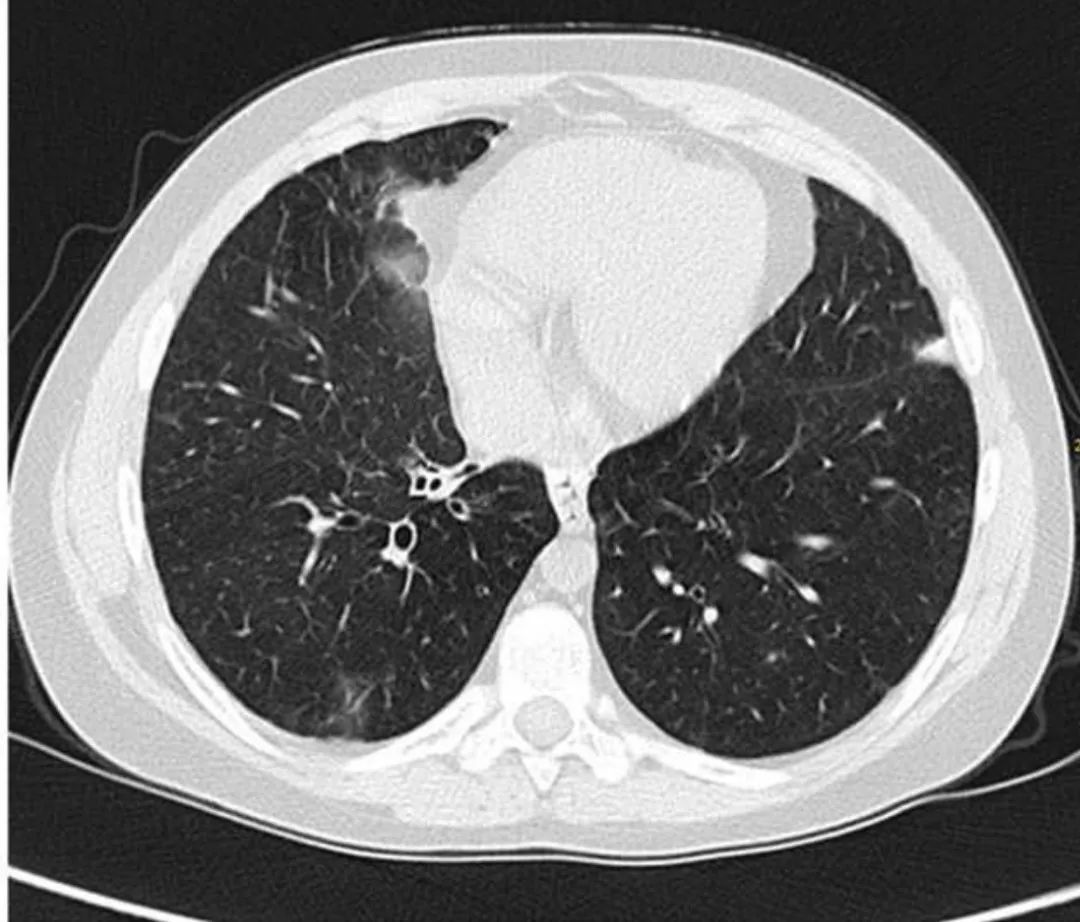

胸部CT显示磨玻璃样不透明实变区域,肿胀,支气管扩张。